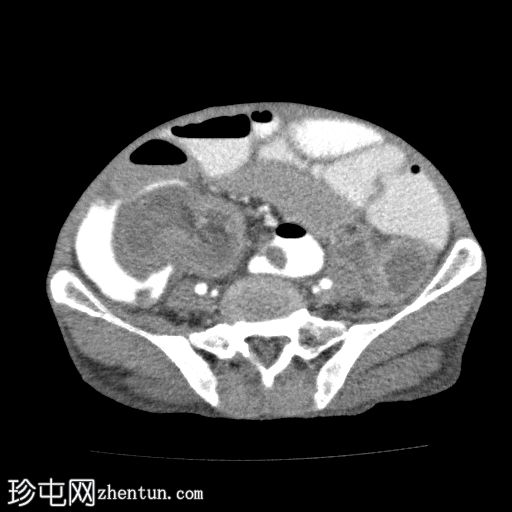

轴位增强扫描

动脉期

回肠肠袢套入盲肠,形成肠套叠形态,轴位和纵位图像分别可见靶征和腊肠征或假肾征。